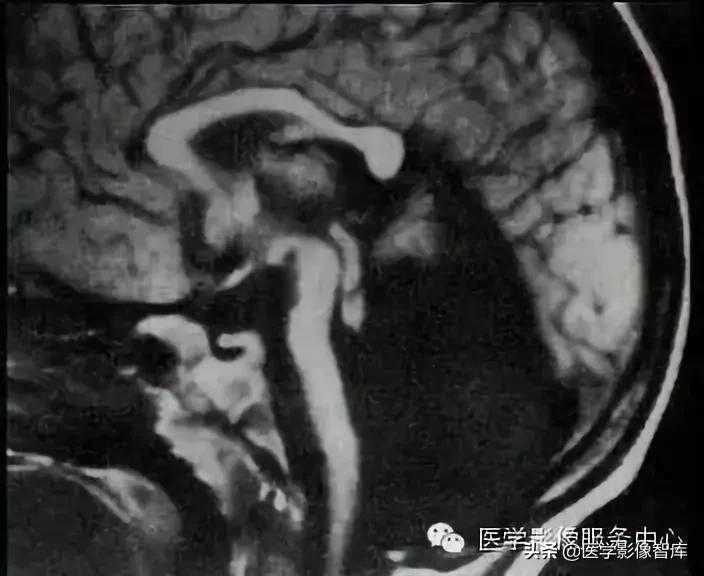

Chiari 畸形 又称小脑扁桃体下疝畸形,是后脑的先天性畸形。 Chiari 畸形的根本原因 是由于后颅窝先天发育不良、容积小而使小脑扁桃体下部疝入到枕骨大孔所致。 其病理特点 是小脑扁桃体下部疝入到椎管内,桥脑、延髓和第四脑室延长、扭曲,并向椎管内移位。此畸形大约56%伴有脊髓空洞畸形。

Chiari畸形 Ⅱ型 Chiari畸形 Ⅱ型为最常见的类型。 病理改变: 在I型的基础上延髓、脑桥下部向下移位,第四脑室下移延长。大多数患者合并脊髓脊膜膨出,几乎所有患者均合并脊髓空洞和脑积水,本型尚可合并颅内其他畸形。